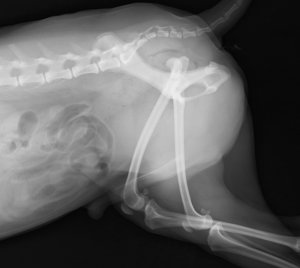

脱臼時のレントゲン画像

エーマースリング包帯後のレントゲン画像